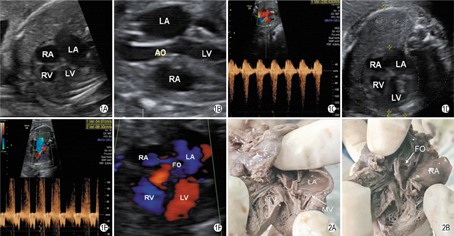

孕妇,21岁,孕28+1周,孕1产0,无家族性遗传病史及早孕期放射线接触史,血清弓形虫、风疹病毒、巨细胞病毒、单纯疱疹病毒检测均阴性。当日外院超声检查发现胎儿心脏饱满来我院就诊,超声检查:胎儿心脏位置正常,四腔心切面左房和左室大(图1A),大动脉关系正常,肺动脉内径正常(4.9 mm),主动脉瓣环细窄,瓣叶增厚,回声增强,开放明显受限,主动脉根部内径2.7 mm,升主动脉狭窄后扩张内径5.0 mm(图1B),横弓中远段内径偏细,横弓部内径2.8 mm,峡部内径2.3 mm,降主动脉内径3.7 mm,CDFI示主动脉瓣口仅见细小血流束通过,流速230 cm/s(图1C),并可见大量反流。二尖瓣瓣叶及瓣下腱索明显增厚,回声增强,瓣膜开放明显受限(图1D),CDFI示收缩期二尖瓣可见大量反流束,反流束达左房顶,二尖瓣瓣口血流速度略增快,流速为80 cm/s(图1E)。左心室内膜回声增强,左室壁运动幅度减低。肺静脉入左房处扩张,CDFI示收缩期可见左房内血流逆向灌注肺静脉内,PW示肺静脉频谱异常,心室收缩晚期和心房收缩期呈反向波形。卵圆孔小,血流束细小(1.5 mm)(图1F)。余胎儿结构未见异常。超声心动图提示:二尖瓣发育不良,二尖瓣重度反流,主动脉瓣重度狭窄,左心增大(巨大左房),卵圆孔小,综上符合二尖瓣发育不良综合征。

超声检查后7 d,在我院行羊膜腔内注射利凡诺引产,经阴道分娩一死产男婴,外观无异常。尸检显示:左房大,二尖瓣瓣叶及瓣下腱索明显增厚(图2A),卵圆孔小(图2B),证实超声诊断结果。